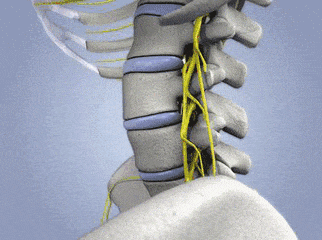

正常的颈椎是一个“C”型结构,颈椎有一个向前凸起,这是它的力学结构基础。这个“C”型的生理弧线保证了颈椎高度的灵活性和稳定性,这也是人体生理和功能的需要。 也正是由于这个生理弧度的存在,使得组成颈椎的7块小骨头能够承担整个头颅的重量,并完成各种动作。颈椎曲度是由于颈4至颈5椎间盘前厚后薄形成的,这也是人体生理结构的需要,同时不会让颈椎间盘突出。 但是,当由于各种原因颈椎曲度变直甚至颈椎反弓时,这个完美的弧形就不存在了。此时,颈椎不再拥有承受头颅重量的能力,不再能够缓冲压力,不再拥有颈4、颈5椎间盘前厚后薄的结构等,从而颈椎会发生退行性改变、颈间盘突出,造成疼痛、头晕、麻木等。 2. 颈椎曲度变直的原因 前凸的颈椎正像一张完美的弓形,而维持颈椎曲度的肌肉、韧带、椎间盘等软组织就像是拉紧的弓弦。这些结构的共同作用,维持了颈椎力学结构的稳定和神经管道的通畅。 当我们平视时,头颅的重心正好落在身体正中。而当我们长期伏案低头时,重心前移,力矩拉长,从而造成了软组织的疲劳,引起疼痛与不适。 久而久之,就如长期拉伸的皮筋一样,最终失去弹性,丧失了维持颈椎正常曲度的能力。从而进入了一个恶性循环,这就是我们常说的颈椎退变。 颈椎退变进一步的加重,则可导致椎间盘突出、骨赘形成、韧带肥厚等,从而对脊髓、神经、血管等重要结构造成挤压,造成肢体麻木、感觉活动功能异常等各类临床症状。 据研究,当我们平视前方时,我们颈椎所承受的负荷大约为5kg,而当我们以低头60°的姿势看手机时,颈椎所承受的负荷甚至可达到27kg。 27kg,这比我们举重比赛常用的最重的红色杠铃片还要再重2kg。按照以上的人均手机使用数据,合以目前我国的平均寿命计,约有985万分钟的时间在低头玩手机中度过。再算上工作、阅读等其他时间,相当于我们戴着一片杠铃一般的枷锁度过20~30年的有期徒刑。 根据颈椎病的不同临床表现,可以分为四大类: 1 颈型颈椎病 正常颈椎曲度 颈椎生理曲度变直 颈椎反弓 2 神经根型颈椎病 3 脊髓型颈椎病 4 其他型颈椎病